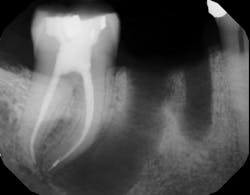

If definitive crown placement is delayed and the patient has excessive forces on the tooth or suffers from direct trauma, the tooth can fracture. In many cases, a decision must be made upon full bone healing versus the likelihood of crown fracture (figure 3–6). In addition, most studies show that full-coverage crowns are a main factor in determining long-term success of root canal therapy, with successes ranging from 92% for teeth receiving crowns compared to 35% for those not receiving crowns after a one- to five-year follow-up.2 In another study on molar teeth five years after root canal therapy, teeth that had crowns placed had a success rate of 78% versus 36% without crown coverage.3